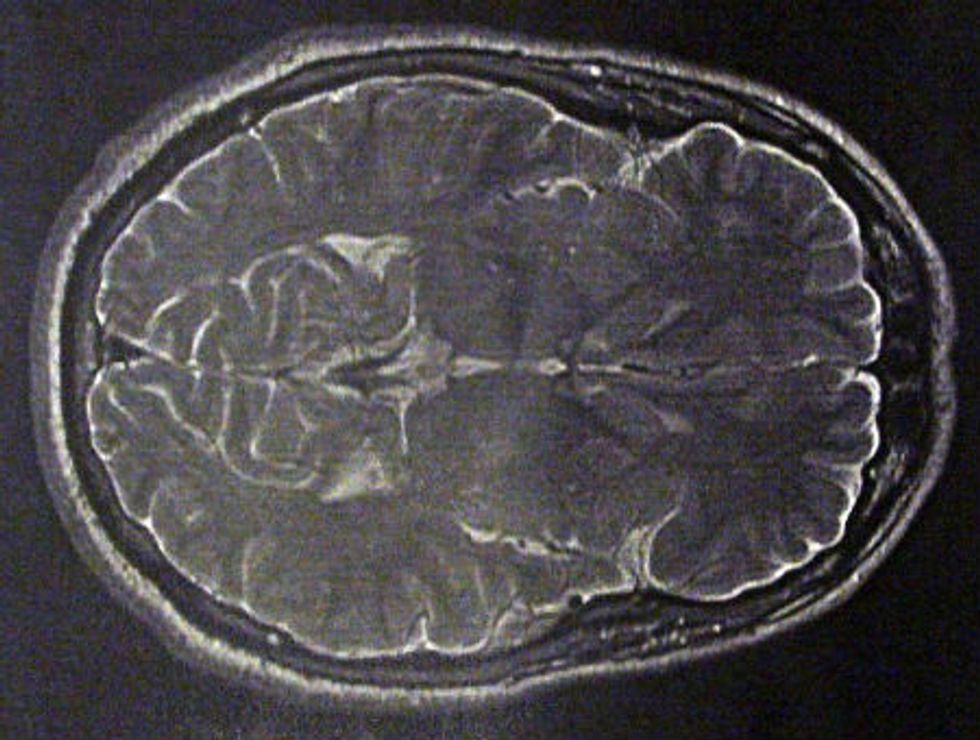

From www.annsaudimed.net

Reversible Brain Shrinkage Documented by Computerized Tomography Signs Brain Is Shrinking What are the signs of cognitive decline? A mild degree of brain atrophy is not always a concern. Brain atrophy (cerebral atrophy) is a loss of neurons and connections between neurons. Learn what happens when your brain shrinks, along with ways to prevent a shrinking brain. Different conditions cause brain atrophy,. Find out what to expect and how you can. Signs Brain Is Shrinking.